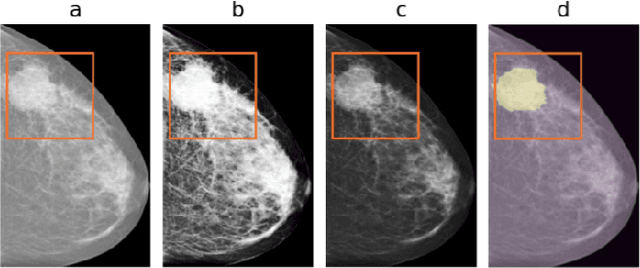

Abstract:Limited amount of data and data sharing restrictions, due to GDPR compliance, constitute two common factors leading to reduced availability and accessibility when referring to medical data. To tackle these issues, we introduce the technique of Learning Using Privileged Information. Aiming to substantiate the idea, we attempt to build a robust model that improves the segmentation quality of tumors on digital mammograms, by gaining privileged information knowledge during the training procedure. Towards this direction, a baseline model, called student, is trained on patches extracted from the original mammograms, while an auxiliary model with the same architecture, called teacher, is trained on the corresponding enhanced patches accessing, in this way, privileged information. We repeat the student training procedure by providing the assistance of the teacher model this time. According to the experimental results, it seems that the proposed methodology performs better in the most of the cases and it can achieve 10% higher F1 score in comparison with the baseline.